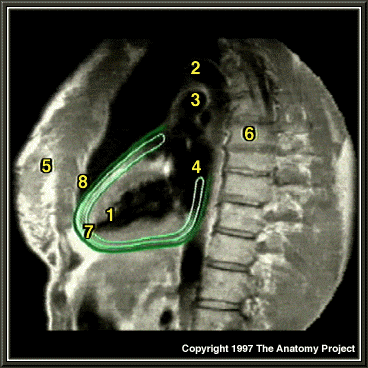

MRI of chest, lateral view

Left ventricle

Aorta

Pulmonary trunk

Left atrium

Breast

Spinal column

Serous pericardium (light green)

Fibrous pericardium (dark green)